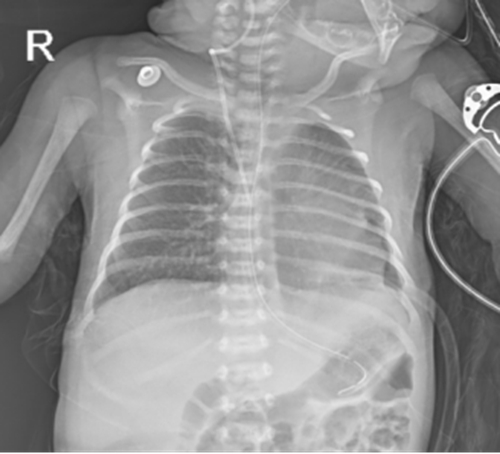

孕39周,胡女士在青島婦兒醫(yī)院產(chǎn)科中心順利剖宮產(chǎn),分娩一名女嬰。出生后,小兒心胸外科救治團隊“接棒”為患兒進行胸腔鏡下膈疝修復術,回納疝內(nèi)臟器、修復缺損。手術順利,寶寶各項生命體征平穩(wěn)。經(jīng)過精心護理,目前已康復出院。